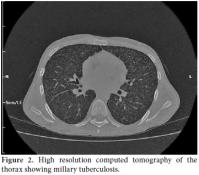

A 22-year-old male patient was presented to the emergency room of our hospital with complaints of fever, headache, and fatigue which had been occurring for 10 days. The medical history revealed that he had been diagnosed as having Behçet’s disease in 2007 and had been using prednisolone since the time of diagnosis. The dosage of prednisolone was increased up to 64 mg/day by the supervising clinician. Cyclosporine-A had been added to the treatment at 100 mg/day two months previously due to eye involvement but was discontinued after one week due to side effects of fever, fatigue, and headache. The patient was prescribed azathioprine at 100 mg/day on the follow-up visit, and he had been using this drug for nearly 10 days prior to being admitted to our hospital. The physical examination findings revealed a body temperature of 39.8 °C, arterial blood pressure of 110/70 mmHg, and a heart rate of 112/per minute. Neck stiffness was minimally positive. He had swelling and sensitivity on palpation in the right scrotal region that had started three months earlier. Laboratory examinations were as follows: leukocyte count 7.400/mm3, erythrocyte sedimentation rate 87 mm/h, C-reactive protein: 13.4 mg/dl in cerebrospinal fluid (CSF) analysis, leukocyte count: 20/mm3, protein: 200 mg/dL, and glucose: 27 mg/dL (blood glucose: 94 mg/dL). There was no growth on the CSF culture. A chest X-ray was normal. Since the CSF findings and physical examination results could not rule out bacterial meningitis, he was started on ceftriaxone 2x2 gr intravenously. He had no regression of complaints in the first week of treatment, and his antibiotic treatment was discontinued. Internal disease and neurology consultations in conjunction with the clinical findings and CSF results led to a diagnosis of neuro-Behçet’s disease. Scrotal ultrasound screening was consistent with epididymitis. A large number of leukocytes were observed in the material aspirated from the testis (90% lymphocyte in nature). Ehrlich- Ziehl-Neelsen (EZN) staining detected acid-resistant bacteria. Treatment with isoniazid, ethambutol, pyrazinamide, and rifampicin was initiated under the diagnosis of testis tuberculosis. Subsequently, chest high resolution computed tomography (HRCT) and brain magnetic resonance imaging (MRI) were done. The chest HRCT result was consistent with miliary tuberculosis (Figure 1), and the brain MRI revealed findings were consistent with tuberculous granuloma and tuberculous meningitis (Figure 2). The vertebral MRI showed that widespread lytic lesions in the vertebra corpuses and the tissue swelling adjacent to the vertebra were consistent with Pott’s disease and spinal granuloma (Figure 3a and 3b). Based on these examinations, the patient was considered to have disseminated tuberculosis (testicular tuberculosis, miliary tuberculosis, tuberculosis meningitis, spinal granuloma, and Pott’s disease). The anti-tuberculous treatment was revised with the ethambutol being replaced by streptomycin. The patient’s body temperature returned to normal on the eighth day of treatment. The patient, whose general condition was observed to improve, is still receiving the treatment.